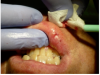

Topical anesthetic was applied to the lesion (Figure 5). Local anesthesia with 2% lidocaine with a 1:100,000 epinephrine mixture was administered by infiltration (Figure 6). Note bleeding at the injection sites in Figure 6 and Figure 7. This reminded the surgeon to be especially careful and mindful of the patient’s condition, which required anticoagulants.

Figure 5 Topical anesthetic was applied prior to administering local anesthesia.

Figure 5

Figure 6 Local anesthesia was given by infiltration. Note the bleeding in the injection sites; the surgeon had to be mindful of the patient’s history of taking blood thinners for his atrial fibrillation.

Figure 6